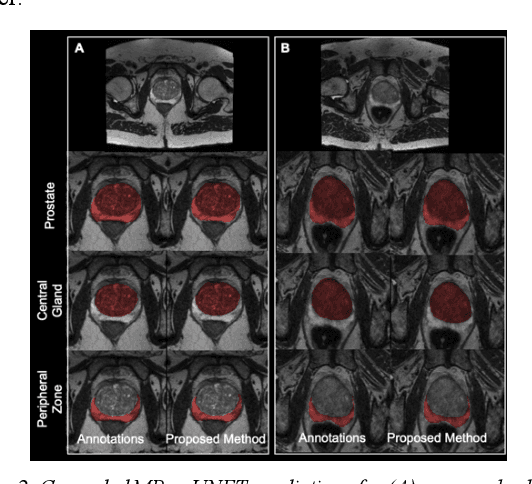

Abstract:Multi-parametric MR images have been shown to be effective in the non-invasive diagnosis of prostate cancer. Automated segmentation of the prostate eliminates the need for manual annotation by a radiologist which is time consuming. This improves efficiency in the extraction of imaging features for the characterization of prostate tissues. In this work, we propose a fully automated cascaded deep learning architecture with residual blocks, Cascaded MRes-UNET, for segmentation of the prostate gland and the peripheral zone in one pass through the network. The network yields high Dice scores ($0.91\pm.02$), precision ($0.91\pm.04$), and recall scores ($0.92\pm.03$) in prostate segmentation compared to manual annotations by an experienced radiologist. The average difference in total prostate volume estimation is less than 5%.